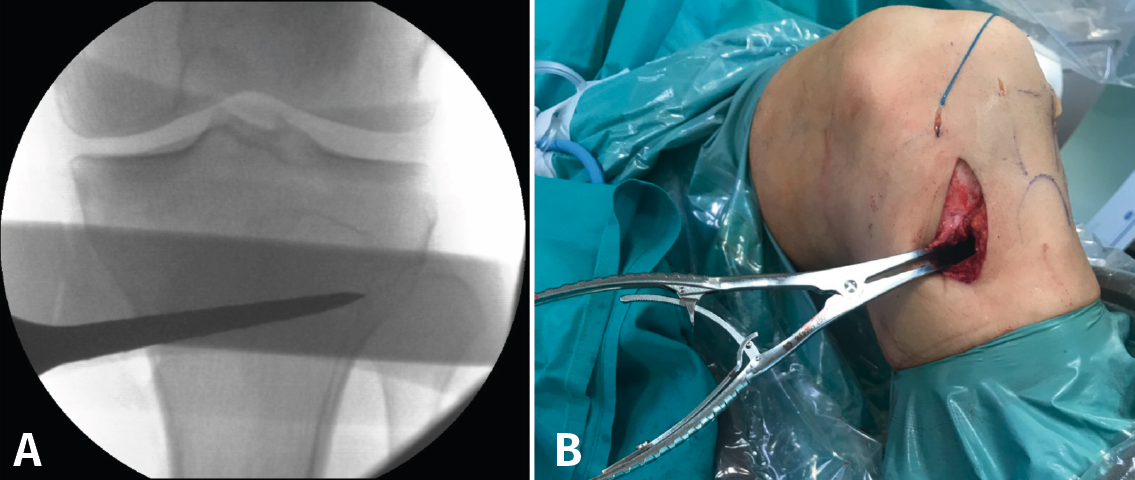

Posteriormente, bajo control radioscópico, se realiza la osteotomía apoyando la sierra por debajo de la aguja guía, llegando hasta 1 cm de la cortical lateral. Se introducen los escoplos para abrir la osteotomía (Figura 4). El primer escoplo, el más ancho, se introduce primero para comprobar el corte completo de la cortical posterior. Seguidamente, se coloca el medidor del ángulo de apertura (Figura 5A) y, a continuación, se introduce el distractor en la parte posterior de la osteotomía, evitando así un aumento de la PTP (Figura 5B). En este momento, se puede introducir en la apertura de la osteotomía el aloinjerto o sustituto óseo. Los autores utilizan aloinjerto óseo cuando la apertura es mayor de 10°. Antes de colocar y fijar la placa de osteotomía, se realiza el túnel tibial utilizando las herramientas artroscópicas clásicas (Figuras 6A y 6B). Al realizar una osteotomía biplanar, el corte es suficientemente distal como para permitir brocar el túnel tibial de la RLCA sin dificultades.

Figura 5. A: medición del ángulo de apertura de la osteotomía con el medidor; B: colocación del distractor en la parte posterior de la osteotomía, evitando así el aumento de la pendiente tibial posterior.